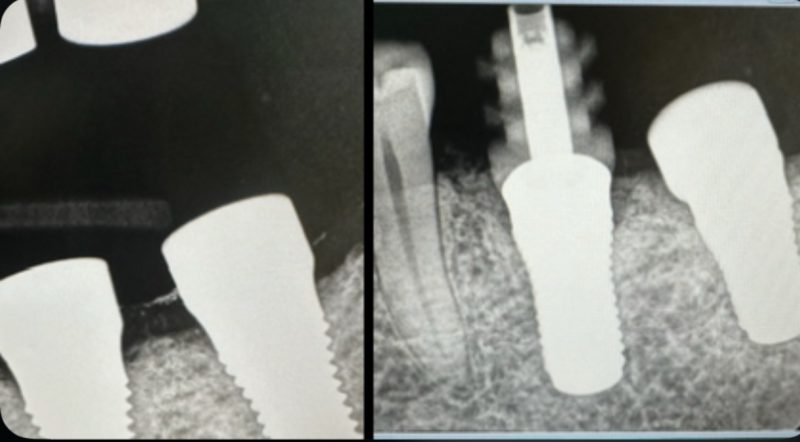

The split image shows a comparison between when I placed it in March, and how it looks now, in August. I placed five healing caps altogether, and no issues with the other four.